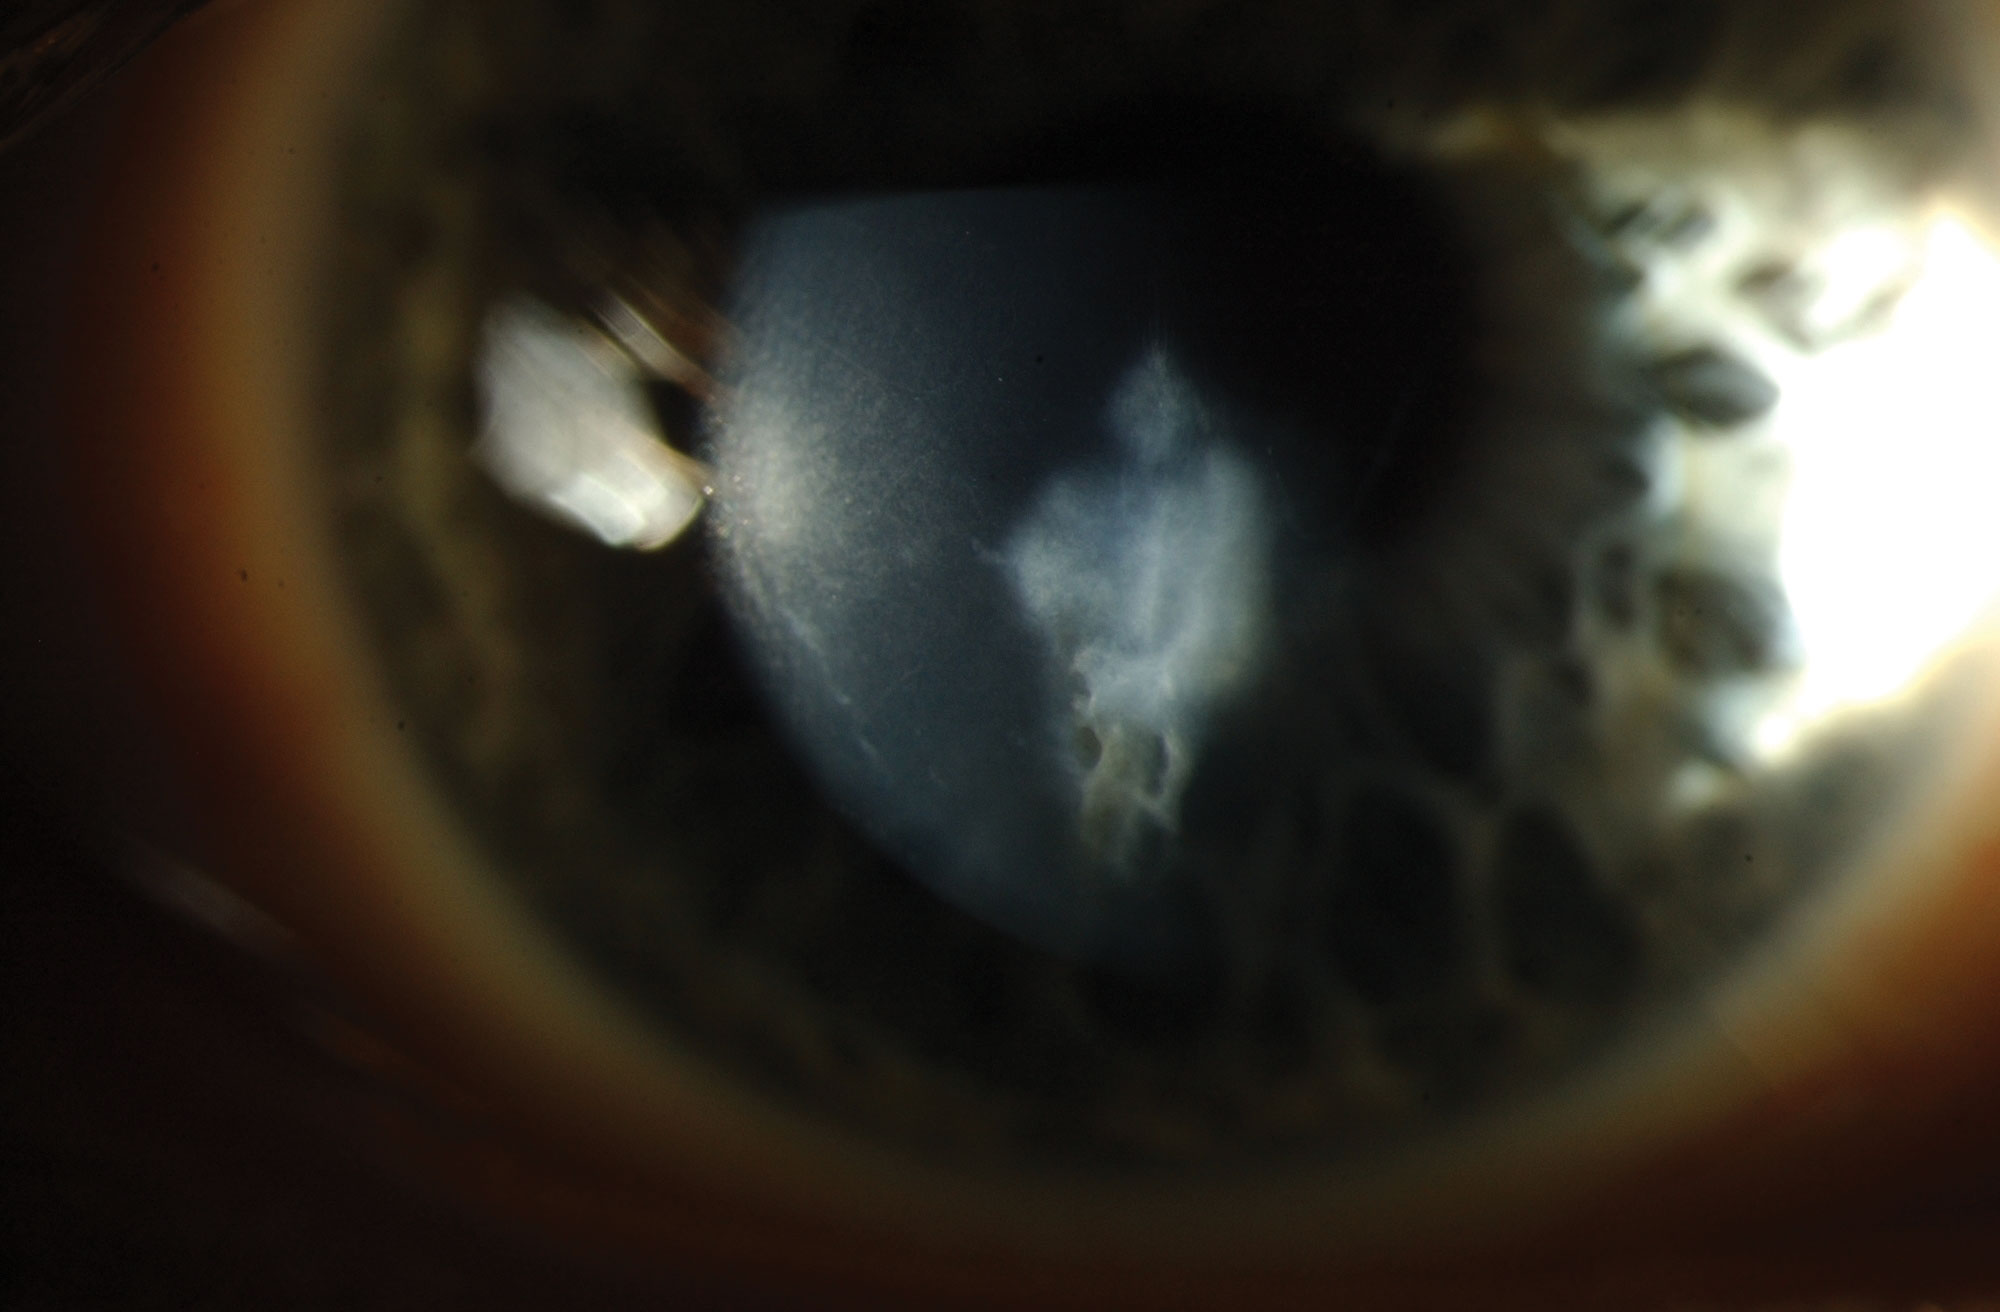

Corneal crosslinking (CXL) is a treatment for keratoconus, a non-inflammatory eye condition in which the normally round dome-shaped cornea progressively thins causing a cone-like bulge to develop.3  The image below shows a corneal scar in advanced keratoconus.

In keratoconus, eye rubbing, genetic predisposition and poorly fitted contact lenses cause eye bulging which results in astigmatism, blurry vision and increased sensitivity to light.4 It typically begins in the teens or 20s (age group: 10-44), and if not diagnosed early could result in significant visual dysfunction, reduced quality of life and permanent changes in lifestyle.5

Some 144 eyes were treated in the nurse-led CXL service from January 2016 to December 2016. Twenty eyes were treated under the supervision of the consultant surgeon or corneal fellow/registrar and 124 eyes were treated by the corneal nurse specialist without direct observed supervision with no adverse events. Three (2.1%) eyes developed corneal infiltrates post operatively which responded well to treatment. Two eyes developed corneal haze which gradually improved after a month (see Figure 3).